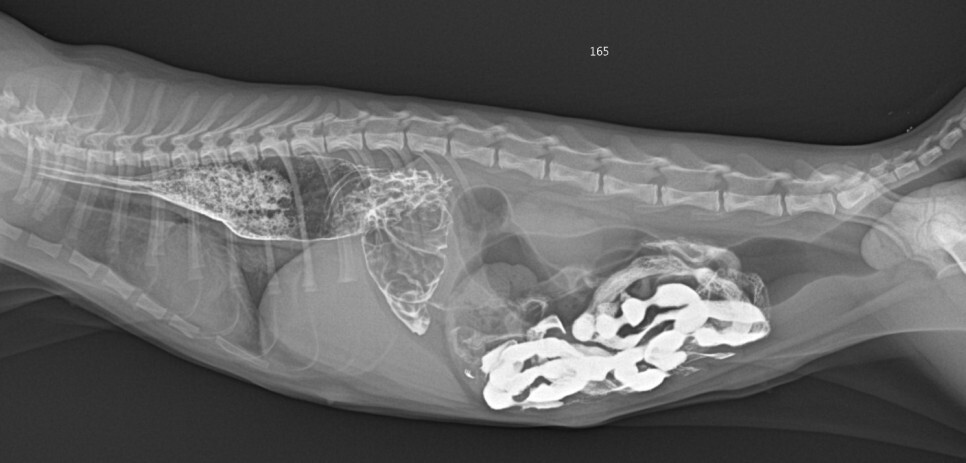

엑스레이 검사에서 식도가 확장되어 있고

위 내에 가스가 많이 차있는 것을 확인할 수

있었습니다. 복강 내 장에서는 이물질도 발

견이 되었습니다.

장폐색을 감별하기 위한 조영 촬영에서

내시경 검사와 마찬가지로 확장된 식도와 식도내강으로 돌출된 위 점막을 확인할 수 있었습니다.

장 내 이물이 발견되기는 하지만 개통에는 문제가

없는 것으로 확인되었습니다.